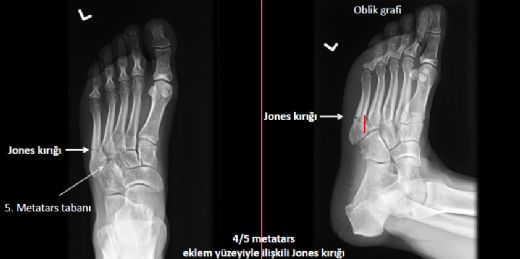

Tanı Yöntemleri Metatarsal kemik kırığının tanısı, genellikle fiziksel muayene ve görüntüleme yöntemleri ile konulmaktadır.